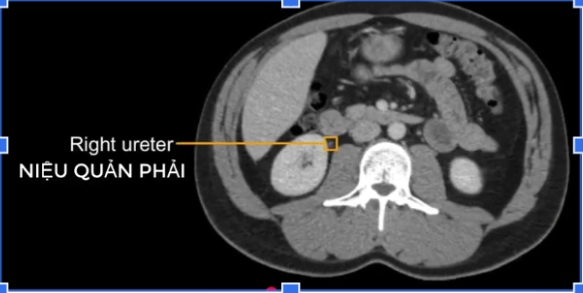

b) Niệu quản ở?